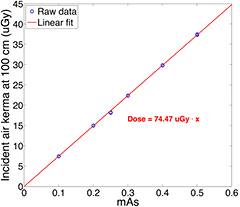

3.4. Radiation dose

The incident air kerma at 100 cm from the focal spot was measured using the dosimeter at different tube mAs at 80 kVp. The tube output varied from 0.1 to 0.5 mAs. For each mAs setting, three measurements were made. Figure 10 plots the relationship between the incident air kerma and the mAs at 100 cm from the central source of the source array at 80 kVp. The measurements show a linear increase with the anode output mAs, as expected. The air kerma reading per mAs at 100 cm was measured to be 74.47 μGy mAs−1.

Figure 10. Experimentally measured relation between the incident air kerma at 100 cm from focal spot and x-ray tube output (mAs). The air kerma is linear to the anode output. The incident air kerma per mAs at 100 cm was measured as 74.47 μGy mAs−1.

In this study, a bench-top DCT system was constructed and used to investigate the feasibility of a stationary DCT using a spatially distributed CNT x-ray source array. One of the key questions investigated was whether the CNT x-ray source array is capable of generating sufficient x-ray output for chest tomosynthesis. Projection images in current commercial DCT systems are typically acquired at 120 kVp and 180 cm SID. The tube output (mAs) is usually derived using automatic exposure control (AEC) from a scout view image (Sabol 2009, Båth et al 2010, Svalkvist et al 2010b, Terzi et al 2013). For instance, the GE VolumRAD DCT system multiply the mAs of scout view by 10, and uniformly distribute the derived mAs into 60 projection views. (Sabol 2009) The scout view is using standard PA CXR technique. Sabol calculated the mean technique of 1.9 mAs and 0.1 mGy incident air kerma for the standard PA CXR used in clinic from 294 adult cases (Sabol 2009). Based on the method to derive tomosynthesis radiographic technique from the scout view, the mean tomosynthesis technique is 0.32 mAs and 16.7 μGy incident air kerma per projection, where the SID is 180 cm and the incident air kerma was measured 25 cm in front of the detector (Sabol 2009). The incident air kerma is a more reliable reference since the tube output in mAs used also depends on the kVp, tube filtration, and SID. For the CNT source array used in this study, the incident air kerma per mAs at 100 cm was measured as 74.47 μGy mAs−1 at 80 kVp. The phantom images in this study were acquired at 0.6 mAs per projection. Using this technique, assuming an average-sized patient with a chest thickness of 25 cm and extending the s-DCT SID to 180 cm as current systems, the incident air kerma is scaled to 18.6 uGy at the patient entrance plane (155 cm from source), which is higher than the mean incident air kerma per projection in the tomosynthesis technique. With larger patient, the mAs per projection needs to be increased accordingly. Therefore, the x-ray output from CNT source array in this s-DCT system is comparable to current clinical tomosynthesis systems. All 75 CNT sources in the tube can be operated stably at this condition with reasonable source-to-source consistency in the cathode-gate voltage and focal spot size.